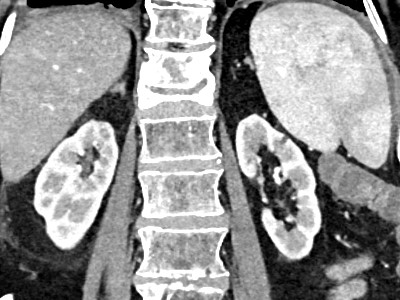

All you need to know about Post Contrast Acute Kidney Injury (AKI)

• PC-AKI is the preferred term for renal function deterioration after contrast medium.

• Important patient risk factors for PC-AKI are CKD and dehydration.